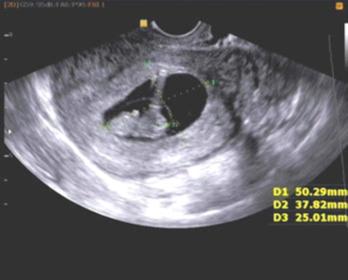

经查,她已停经超过2个月。所以我对小文说:人工流产的最佳时间是怀孕后45天内,你们都停经2个多月了,本身人工流产就很危险,所以风险更大,先去检查。在得到结果后,再决定手术方案。问完诊后,我给小文安排了术前相关检查。

我根据患者妇科检查和B超的结果,显示她已经怀孕60多天了,为了安全起见,需要先口服米索前列醇200 ug,在阴道后穹隆里放一片米索,让它软化宫颈,为手术做准备。然后我告诉小文和小超一些可能在手术中出现的相关风险及术后注意事项,让他们共同签署手术知情同意书,做好积极的术前准备,行阴道冲洗等局部治疗。

做好术前准备后,1小时后在超导可视下进行无痛人工流产,手术成功,术中用负压吸引器吸出一个孕囊,约3.5*4.5 cm,可见胎芽。术中出血约10ml,然后在宫颈内注射缩宫素10 ml,促进子宫收缩。手术后让小文在观察室休息2小时,观察腹痛及阴道出血情况,并给予输液预防感染,促进宫缩等对症治疗。